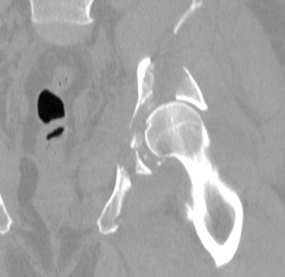

El primer paso para realizar una impresion 3d medica consiste

en la adquisicion de imagenes mediante un aparato de TAC o RNM

En las imagenes que se muestran a la izquierda de este texto se pueden observar los pasos requeridos para obtener impresiones 3d medicas. Todo comienza con la adquisicion de las imagenes por medio de aparatos medicos capaces de realizar reconstrucciones tridimensionales a partir de los diferentes estratos.